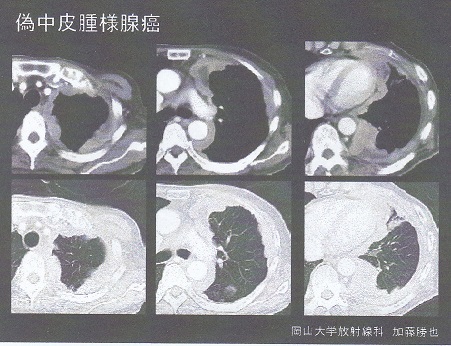

肺癌と中皮腫

① 中皮腫様発育をする肺癌:腺癌が多い

② 中皮腫と似た免疫染色傾向を示す肺癌:多形癌